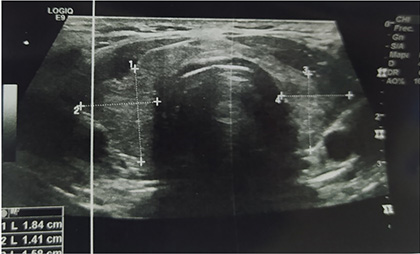

Cuatro meses después del cuadro inicial, el paciente fue hospitalizado nuevamente por cuadro de 4 horas de evolución caracterizado por presentar parálisis flácida de miembros superiores e inferiores, acompañado por parestesias en miembros inferiores, mialgias y disnea, sin alteración de funciones superiores, al examen físico con presión arterial 110/70, frecuencia cardíaca 90 latidos por minuto, tiroides de tamaño normal, sin alteraciones cardiopulmonares, sin temblor distal en manos. Entre los estudios de laboratorios realizados en emergencias destacó la presencia de hipopotasemia severa de 2,0 mEq/l. Con la sospecha de PPHT, se solicitó estudios de función tiroidea con resultados de TSH 0,01 uUI/ml (rango de referencia 0,4 y 4,5), T4 libre 3,09 ng/dl (rango de referencia 0,8 y 1,65), anticuerpos anti TPO 552 UI/ml (rango de referencia 0 a 95) y anti tiroglobulina 211 UI/ml (rango de referencia 0 a 30), tiroglobulina 17 ng/ml (rango de referencia 0 a 55), ecografía tiroidea que reportó de tamaño y morfología normal, sin evidencia de lesiones nodulares (Figura 1), electrocardiograma sin alteraciones (Figura 2). Se inició tratamiento con fármacos antitiroideos y betabloqueadores, además de jarabe de potasio, el mismo que se disminuyó de forma gradual hasta su suspensión. Hasta la fecha el paciente mantiene tratamiento con tiamazol 20 mg por día, con control adecuado de la función tiroidea, sin nuevos episodios de debilidad y/o hipopotasemia. Se presenta la evolución de la concentración de potasio sérico en la Figura 3.